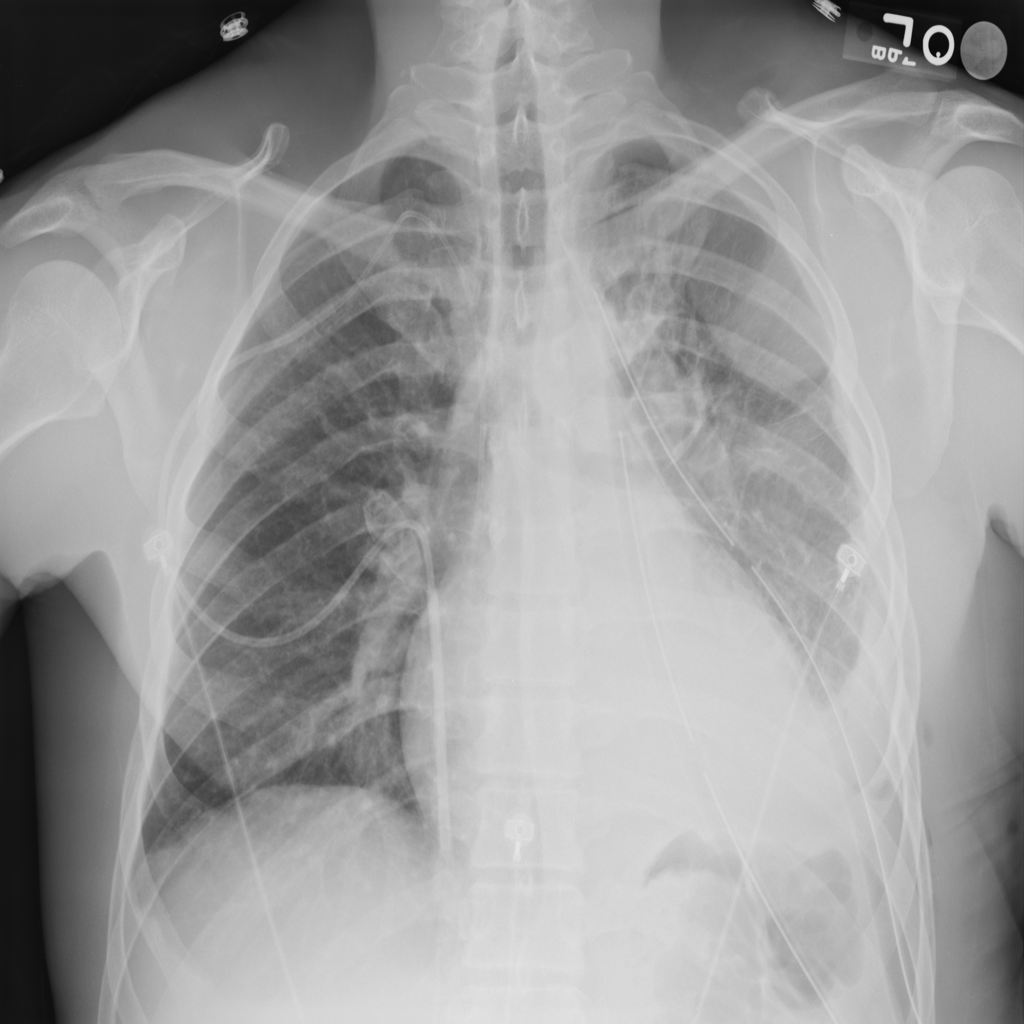

Consolidation

Consolidation refers to air-space filling that makes part of the lung appear denser on imaging.

Showing up to 90 reference images for Consolidation.

PAT-C1A7 · IMG-004Consolidation

PAT-C1A7 · IMG-004

PA